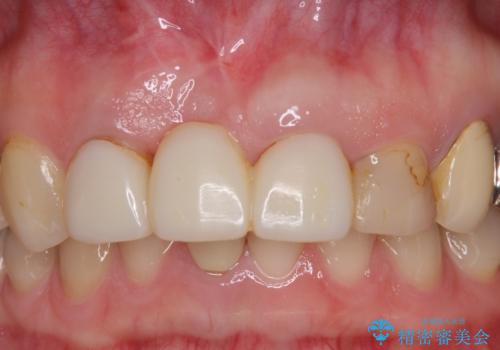

鼻の下を押すと痛い 抜歯を避けてきた歯を抜歯して自然な口元に

- 以前から前歯の根が折れていると言われていたものの放置しており、いよいよ痛みが気になってきたとのことで来院された患者様です。

検査の結果、右前歯の歯根が縦に破折していることが分かりました。

破折している歯は抜歯をし、歯肉が窪んでしまうので、傷口の治りを待って、歯肉移植を行うこととしました。

歯肉移植終了後、オールセラミックブリッジにて補綴することとしました。

歯肉移植により歯肉ラインや歯の形態を整えることができ、ブリッジによる補綴としたことで舞えば全体の色調を整えることができました。